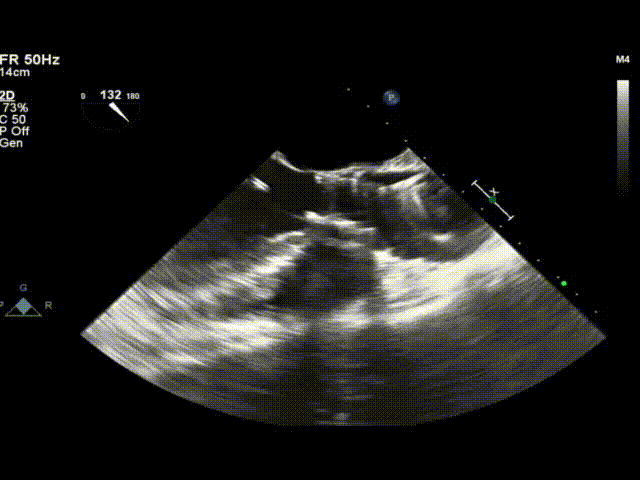

心脏多普勒超声诊断为:重度主动脉狭窄伴中度反流,二尖瓣轻中度反流,三尖瓣轻度反流,左房增大。

超声显示瓣膜形态良好,血流动力学优异